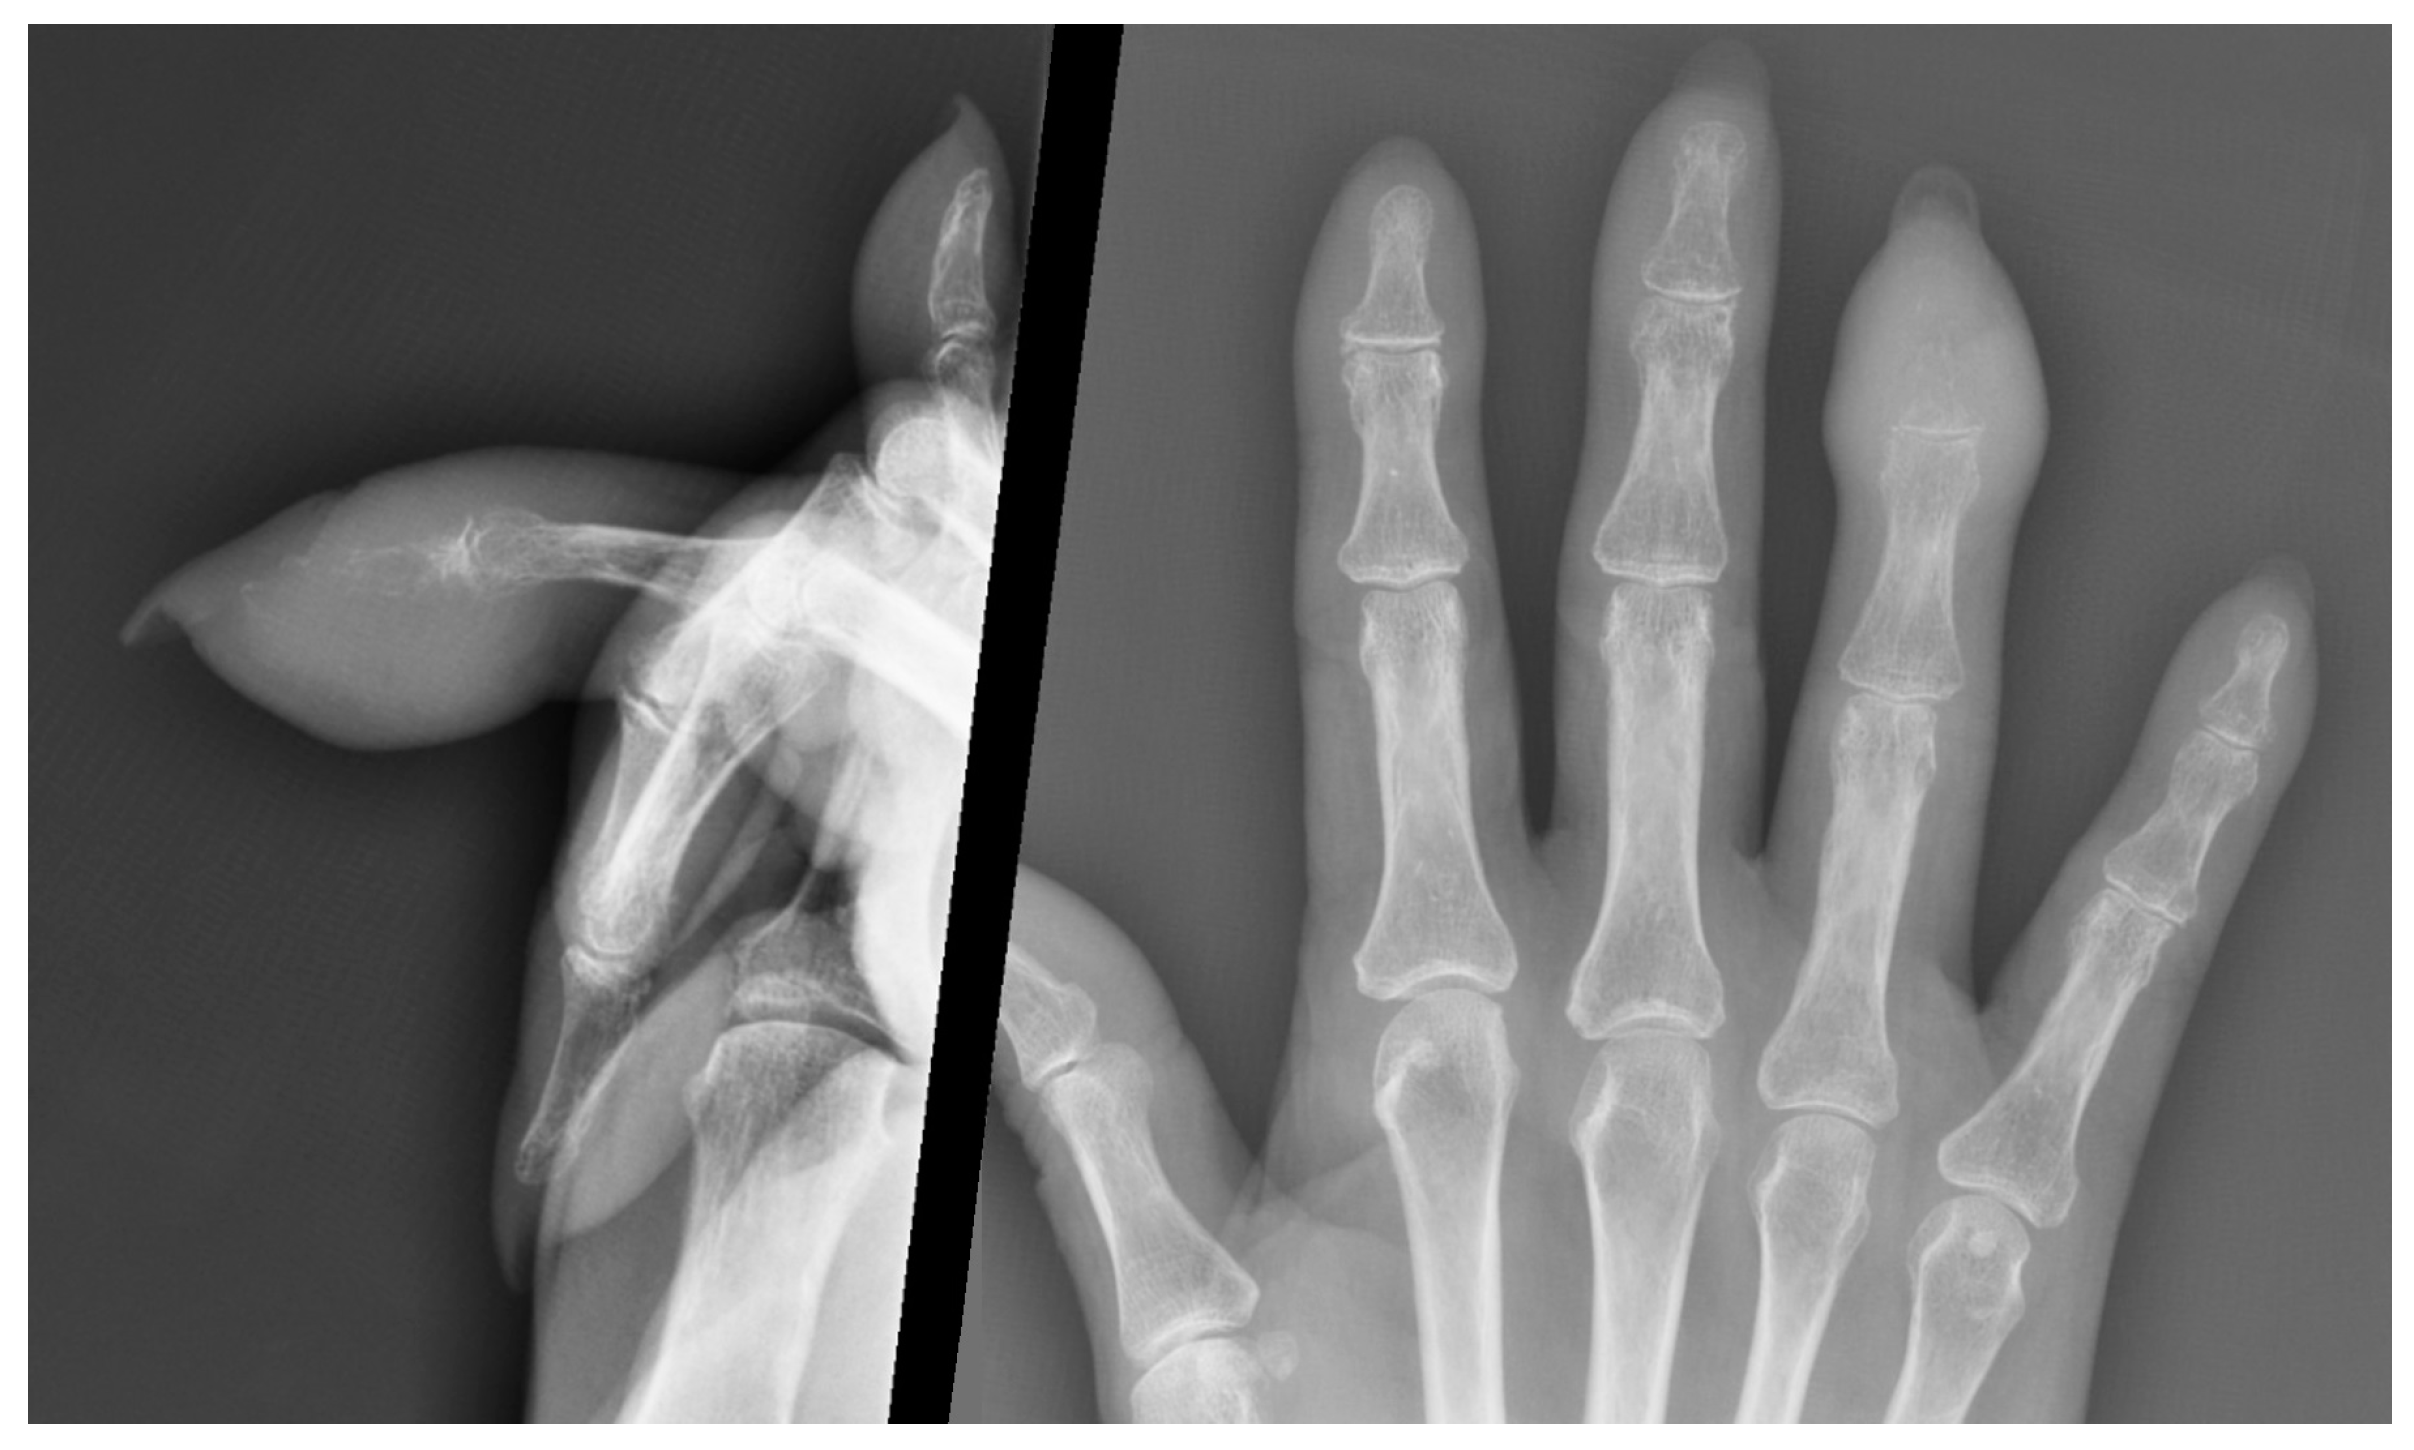

4.2. Imaging